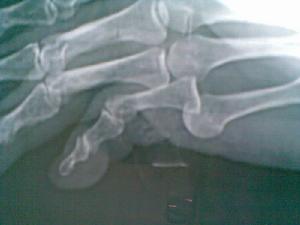

關節指的就是骨關節,正常關節至少包括兩個骨端,相鄰兩骨的關節面呈一凸一凹的對合關係,關節可以產生運動,如屈、伸、收、展運動。關節脫位就是指骨的關節面失去正常的對合關係或者失去部分正常的對合關係。分類

骨關節脫位部位

關節脫位部位比較表